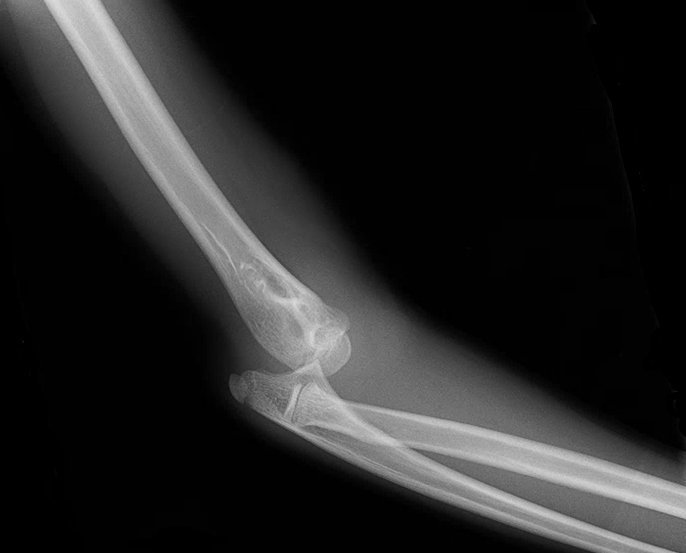

A 13 yo F presents to the ED with R elbow pain after falling off the top of a cheerleading pyramid. Exam shows an obvious deformity of the R elbow with swelling and limited ROM. She is neurovascularly intact distal to the injury. An xray is obtained. What's the diagnosis? (scroll down for answer)

Answer: Supracondylar fracture with posterior elbow dislocation

- Patients present with elbow held in 45 degrees of flexion, with the olecranon being prominent posteriorly